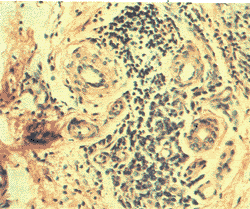

【病理改變】

淋巴是細胞間隙中的組織液,經淋巴管回流入靜脈。淋巴循環亦是人體生理功能性體格循環這一。淋巴系統先天性發育不良或由於某種原因發生閉塞或破壞,所屬遠端淋巴回流即發生障礙,組織間隙淋巴液異常增多。若發生在肢體則受累肢體均勻性增粗,起初皮膚尚光滑、柔軟,抬高患肢水腫可明顯消退。由於積聚的淋巴液富含蛋白質,可高達5.8g/dl,〔正常0.72g/dl〕長期刺激使結締組織異常增生,脂肪組織為大量纖維組織替代。皮膚及皮下組織極度增厚,皮膚表面角化、粗糙、指壓後不發生壓痕,出現疣狀增生物,形成典型的“象皮腫”。感染使炎性滲出液增加,刺激大量結締組織增生,破壞更多的淋巴管,加重淋巴液滯留,增加繼發感染機會,形成惡性循環,致使淋巴水腫日益加重。